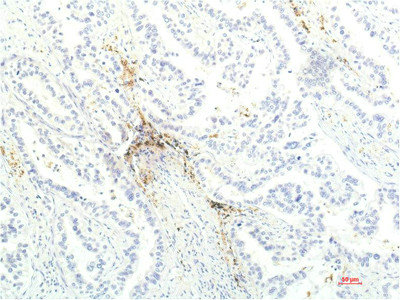

Paraformaldehyde-fixed, paraffin embedded Human liver cancer; Antigen retrieval by boiling in sodium citrate buffer (pH6.0) for 15min; Block endogenous peroxidase by 3% hydrogen peroxide for 20 minutes; Blocking buffer (normal goat serum) at 37°C for 30min; Antibody incubation with _x000D_ JAK1 Monoclonal Antibody, Unconjugated (bsm-33268M) at 1:400 overnight at 4°C, DAB staining.

ApplicationsImmunoFluorescence, ImmunoCytoChemistry, ImmunoHistoChemistry, ImmunoHistoChemistry Frozen, ImmunoHistoChemistry Paraffin

- Applications SupplierIHC-P(1:200-400), IHC-F(1:100-500), IF(ICC)(1:50-200), IF()